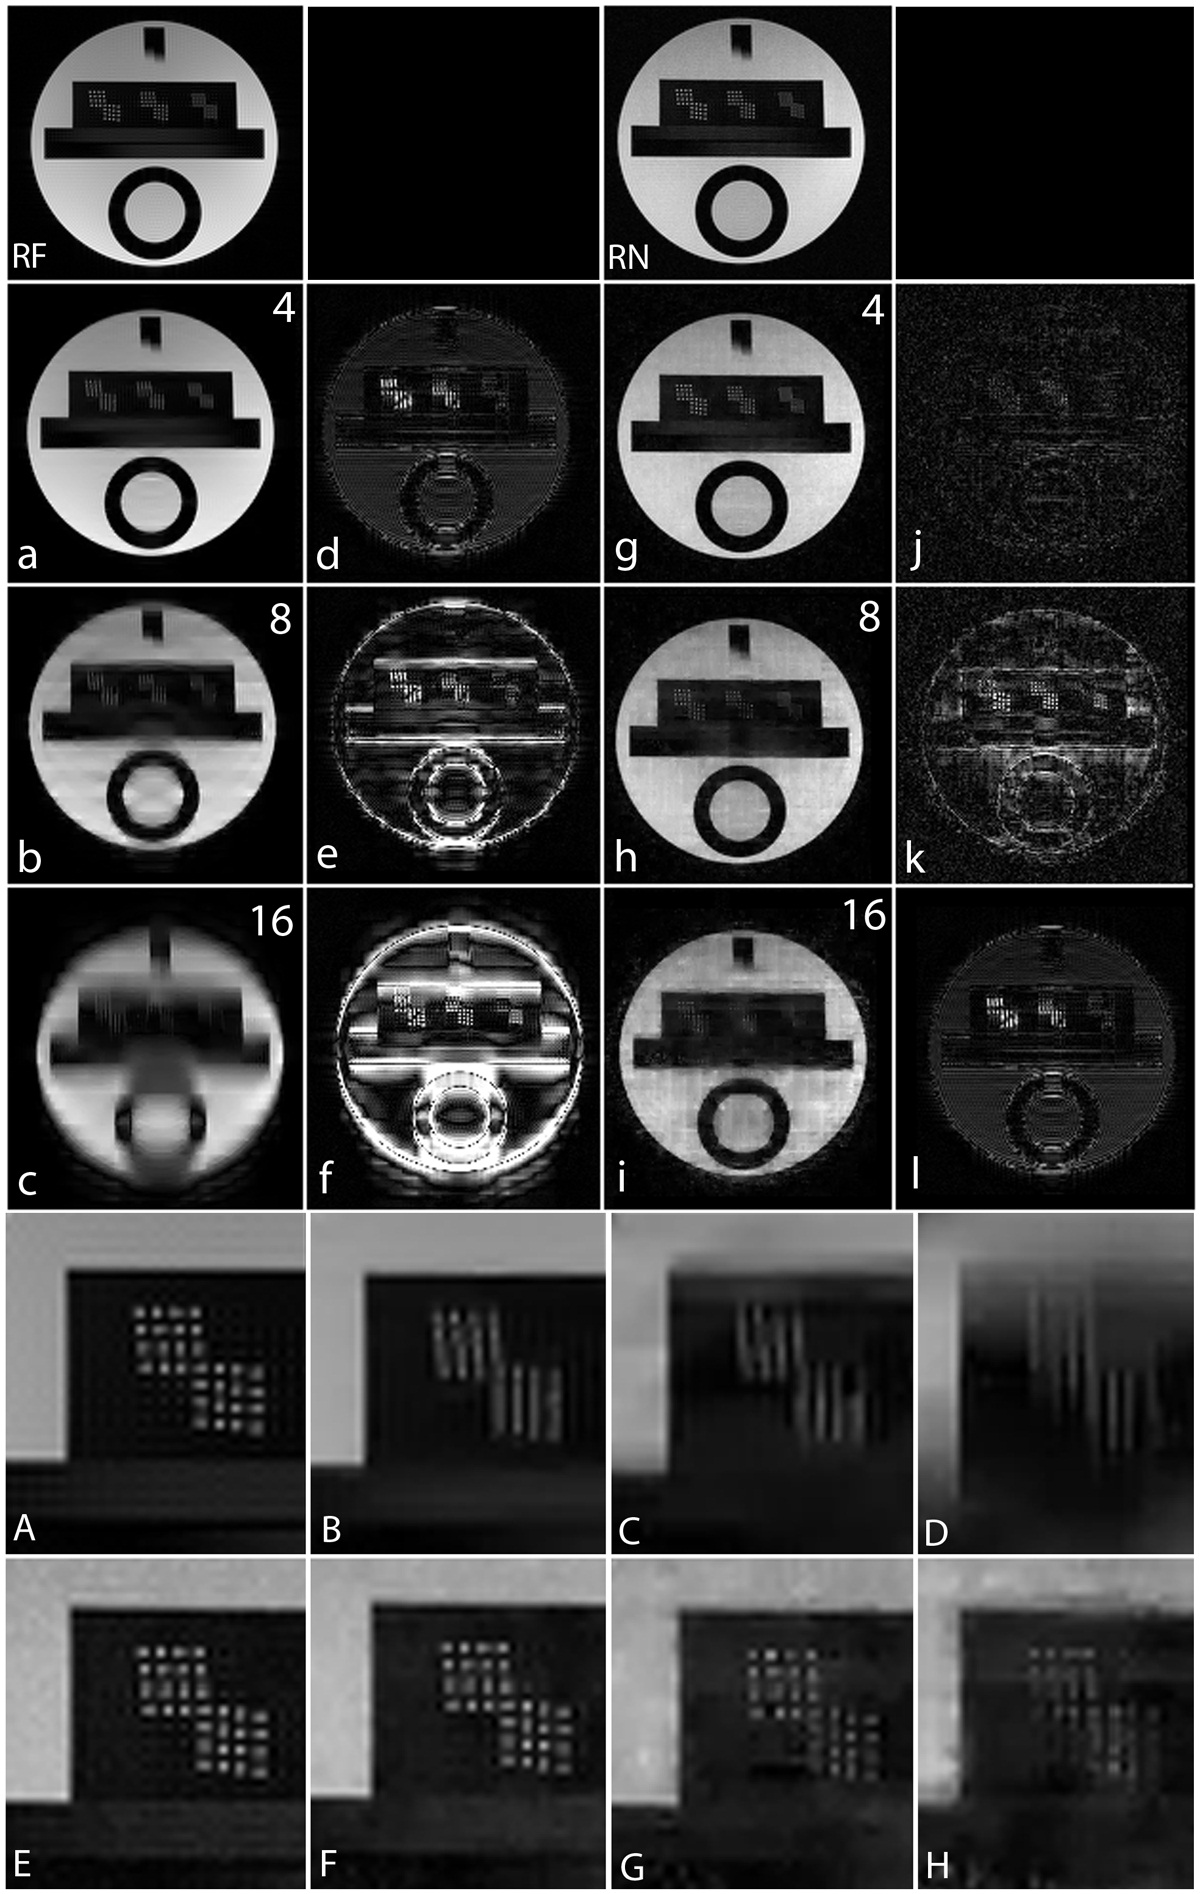

Non-Fourier encoding in general is sensitive to field inhomogeneities, but careful design of the sequence and good shimming can result in high quality images. To reconstruct the noiselet encoded data the inverse Fourier transform was taken along the frequency encoding axis and the inverse noiselet transform was taken along the PE axis. To reconstruct the Fourier encoded data, an inverse Fourier transform was taken along both axes. Fig. 11 shows the images reconstructed from the noiselet encoded data and Fourier encoded data sets. These images demonstrate that the noiselet encoding reconstructions are practically feasible and produce artifact free images. Fig. 11(c) shows a zoomed portion of the noiselet encoded image, while Fig. 11(f) shows a zoomed portion of the Fourier encoded image. The zoomed images reveal that the resolution of the image from noiselet encoding with 256 noiselet excitation is the same as that of the image from Fourier encoding with 256 phase encodes. Fig. 11 (g) and (i) show the T2 weighted images for the brain with noiselet encoding and Fourier encoding, respectively. Fig. 11 (h) and (j) show the T1 weighted images for the brain with noiselet encoding and Fourier encoding, respectively. It is evident from the in vivo images that the proposed noiselet encoding is feasible in practice.

To validate the feasibility of the proposed reconstruction method, we performed retrospective under-sampling on the acquired noiselet encoded data and Fourier encoded data to simulate accelerated data acquisition. After retrospective under-sampling, the unconstrained optimization program (10) was solved using the non-linear conjugate gradient method to reconstruct the desired image for different acceleration factors. Fig. 12 (a)-(c) shows the reconstructed images for the acceleration factors of 4, 8 and 16 on the Fourier encoded data while Fig. 12 (d)-(f) shows the corresponding difference images. Similarly, Fig. 12 (g)-(i) shows the reconstructed images for the acceleration factors of 4, 8 and 16 on the noiselet encoded data, and Fig. 12 (j)-(l) shows the corresponding difference images for noiselet encoded MCS-MRI. These results on the acquired data are consistent with the simulation results and indicate that the noiselet encoding is superior to the Fourier encoding in preserving resolution.

Fig. 12 (A-H) shows the zoomed portion of the reconstructed images with Fourier encoding and noiselet encoding. One can distinguish between the small dots in the zoomed images reconstructed with noiselet encoding while it is difficult to distinguish these dots in the images reconstructed with Fourier encoding. This demonstrates that noiselet encoding is able to preserve resolution better than the Fourier encoding. Fig. 13 show the images reconstructed with Fourier encoding and noiselet encoding for various acceleration factors on the data acquired for one axial slice of the brain. Since the SNR of the in vivo images is less than in the phantom images, reconstruction is shown only up to an acceleration factor of 8. The difference images demonstrate that noiselet encoding outperforms Fourier encoding for all acceleration factors. In particular, at the acceleration factor of 8 the image reconstructed with Fourier encoded data has significantly poorer resolution compared to the image reconstructed with noiselet encoded data.